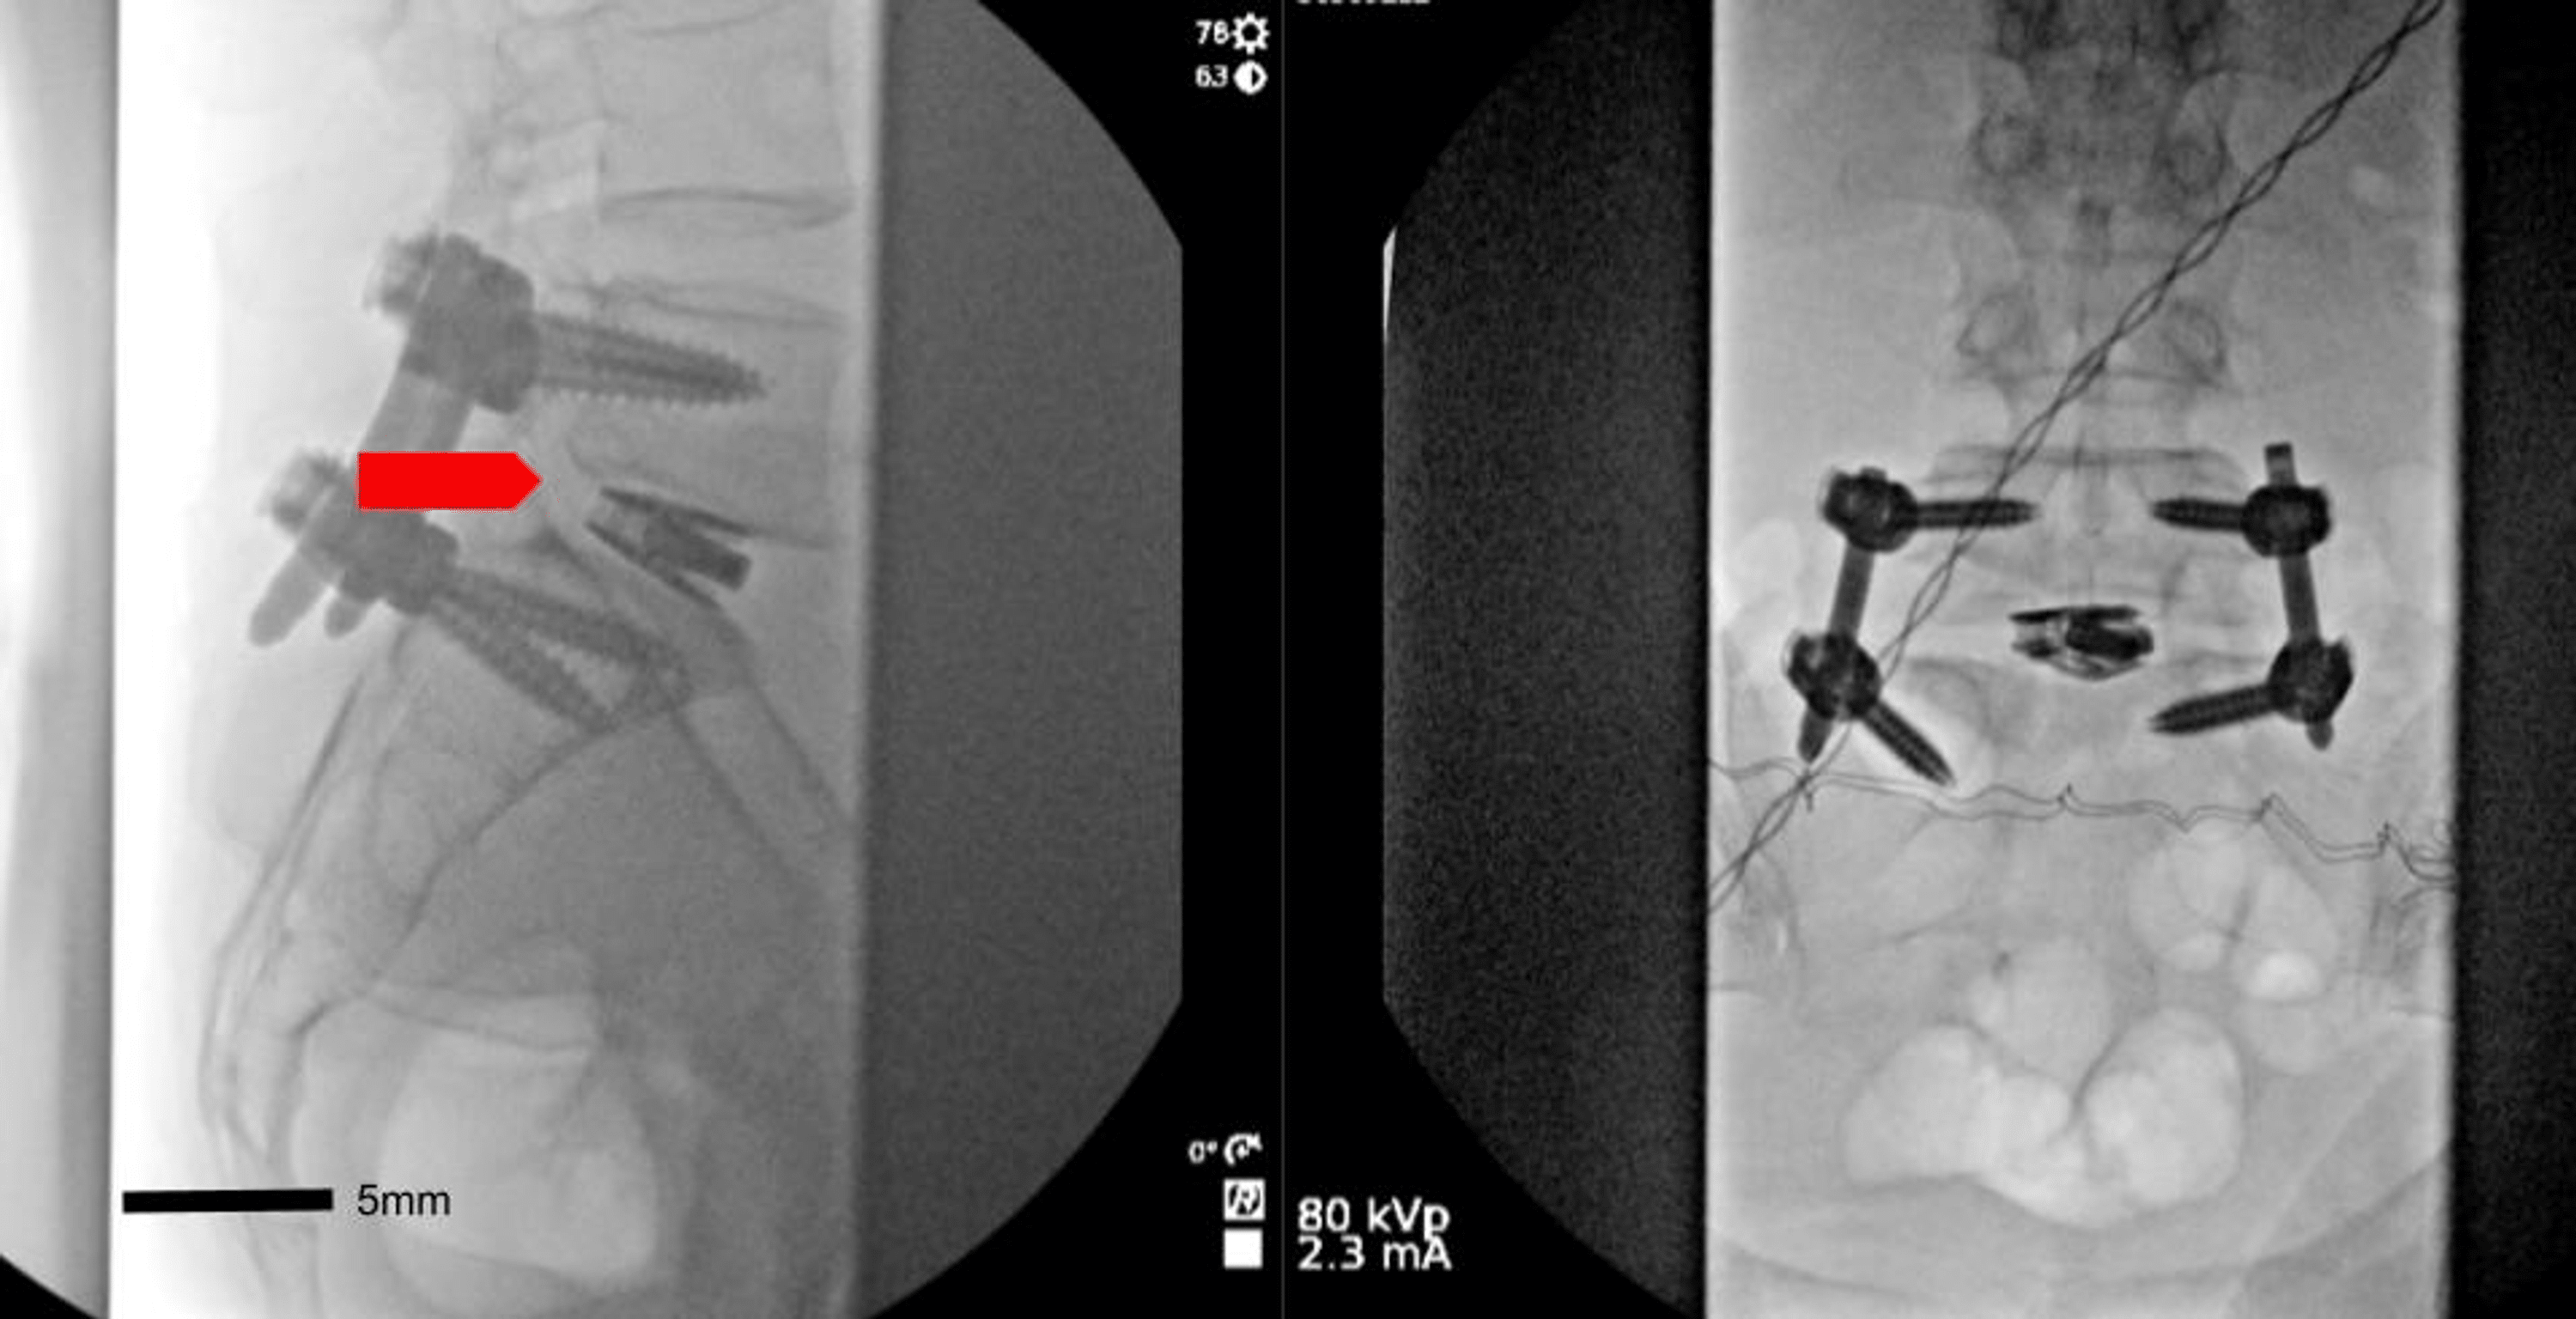

From www.cureus.com

Abnormal L5S1 Facet Joint Orientation as a Harbinger of Degenerative L5-S1 Facet Joint Pain Symptoms  If a spinal nerve is irritated or compressed at the facet joint (such as from a facet bone spur), a sharp, shooting pain. This syndrome is a medical. These symptoms can manifest as dull, aching pain, sharp. Facet arthropathy can cause lower back pain and usually affects a specific part of your spine. The spinal nerves come off the. These. L5-S1 Facet Joint Pain Symptoms.